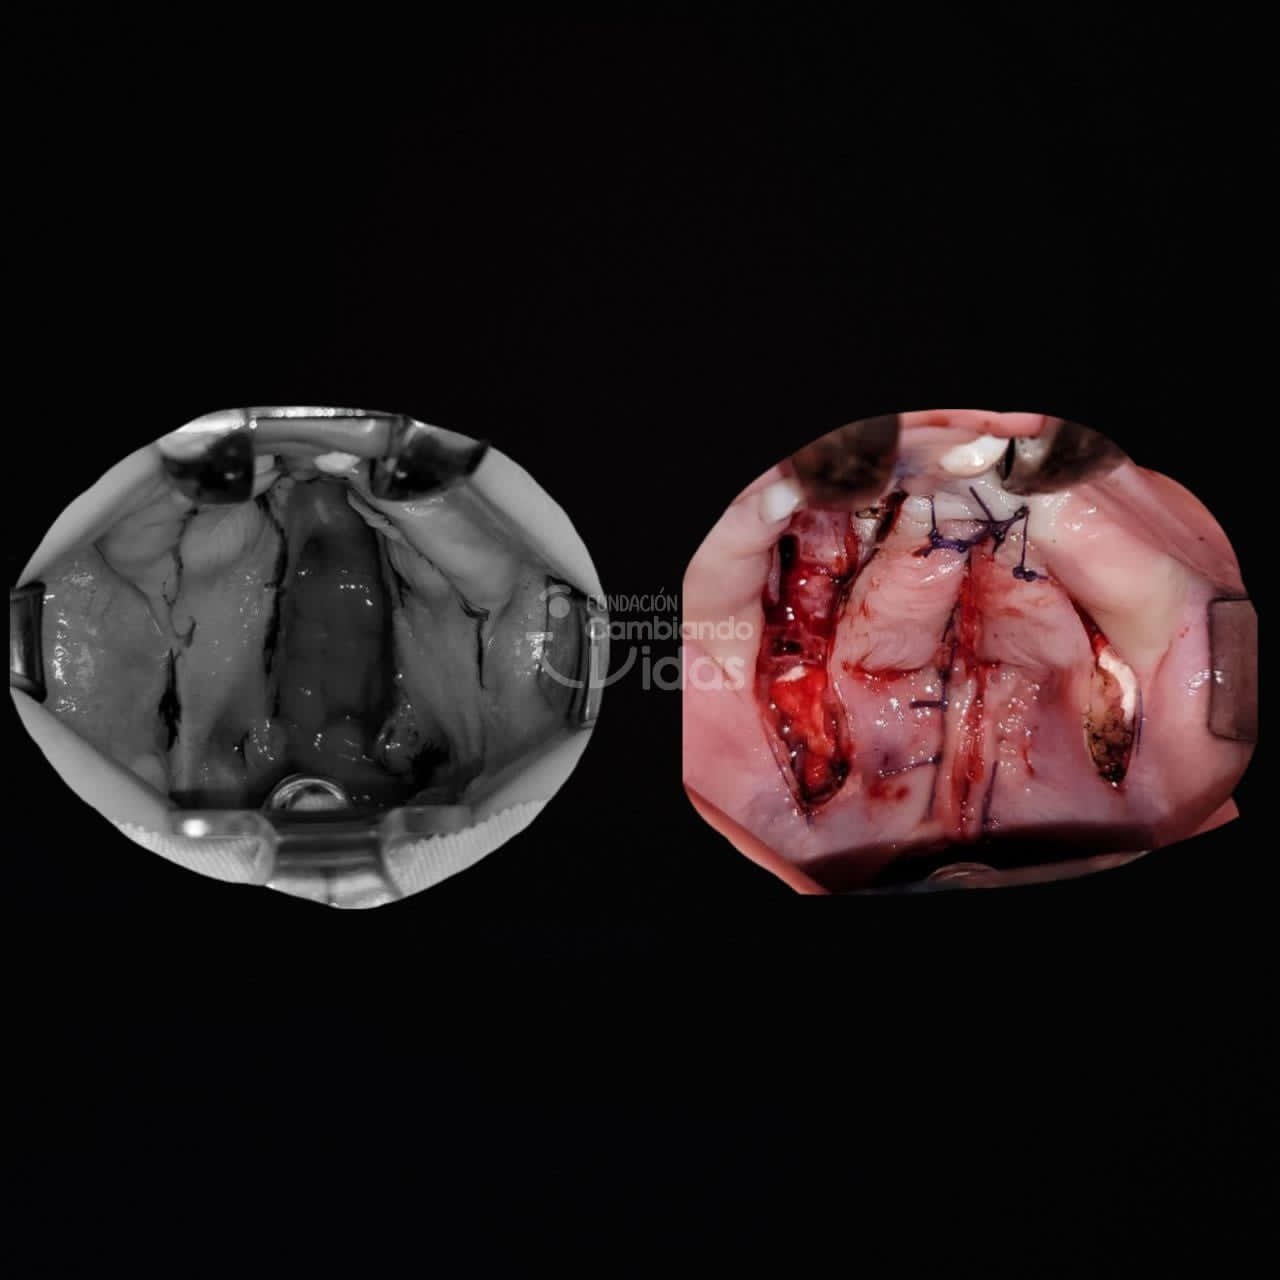

Intervención Quirurgica: Rinoqueiloplastia Secundaria y Palatoplastia Primaria